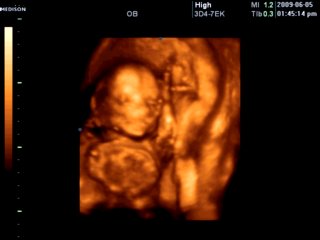

胎儿23周三维彩超图

医生表示,在孕期22-26周即可做彩超排畸检查,因为此时胎儿的肢体及各主要脏器已经全部发育,而且羊水较适合做胎儿畸形筛查,宝宝图像也会更清晰。可以观察到胎儿成长的过程,看看宝宝在腹中的可爱模样。